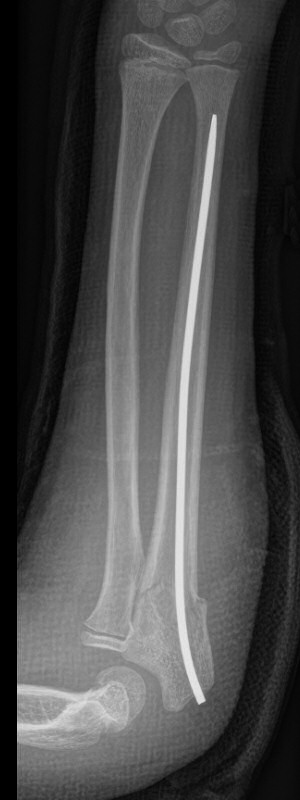

Distala diafysära radius- och ulnafrakturer, opererade med TEN-spikar, sista bilderna läkt efter 7 månader. Alla bilderna är från samma patient.